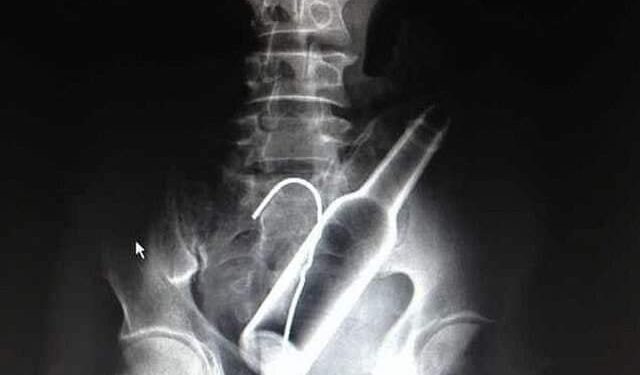

Le practivaron unos Rayos X, que reveló la ubicación de la botella de vidrio, la cual se localizaba entre el recto y el sismoide, por lo que fue necesario que lo interviniera un cirujano para que la pudieran extraer.